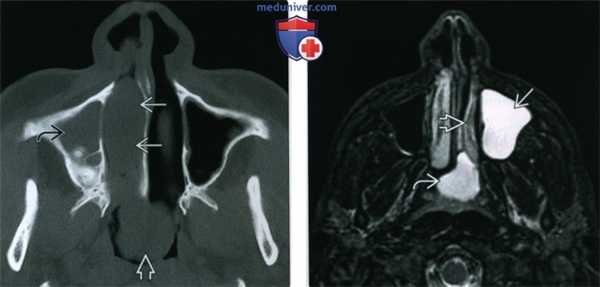

(Слева) При аксиальной «костной» КТ определяются типичные признаки АХП. Пневматизация правой верхнечелюстной пазухи снижена, визуализируется полиповидное мягкотканное образование, пролабирующее в полость носа. Сзади полип пролабирует через хоану в носоглотку.

(Справа) При аксиальной МРТ Т2 FS у ребенка определяется гиперинтенсивный АХП слева. Видны антральный и носоглоточный ва компоненты. АХП гиперинтенсивнен по сравнению с нижней носовой раковиной.